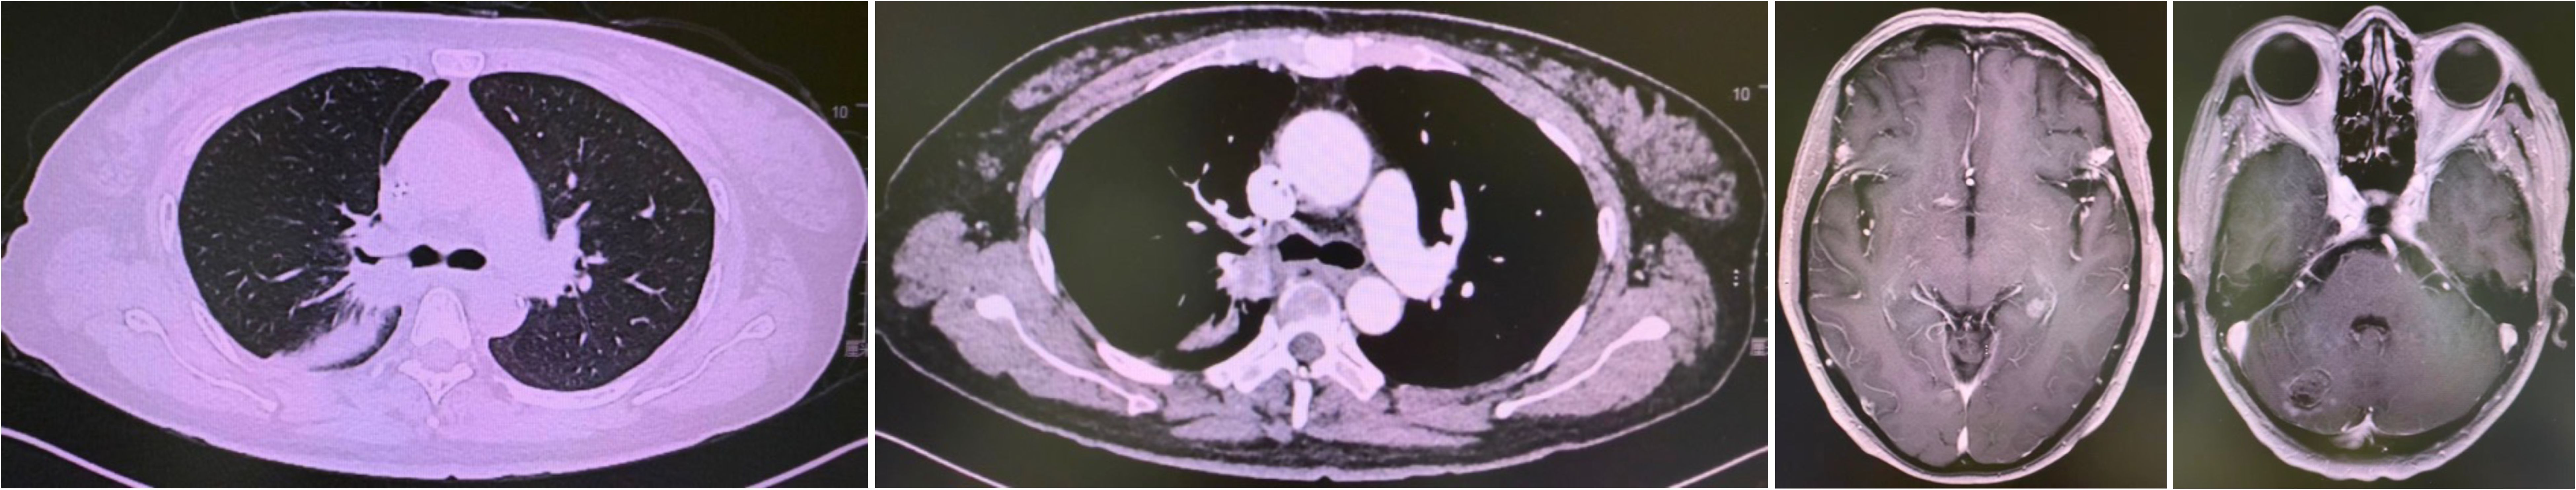

First-line therapy with osimertinib 80 mg once daily was initiated (4). After two months, restaging CT showed partial response with reduction in the lung mass to 28 mm × 25 mm. Follow-up brain MRI confirmed complete resolution of the cerebellar metastasis. The patient remained progression-free for 20 months until June 2020 when repeat imaging demonstrated disease progression (8). (Figure 1).

Figure 1

Four CT scan images from August 2020 showing different cross-sectional views of a patient's chest and head. The scans reveal various internal structures and tissues, with differences in density visible in shades of gray.

Figure 1. Progression after Osimertinib from November 2018 to June 2020. Small cell transformation confirmed by rebiopsy.